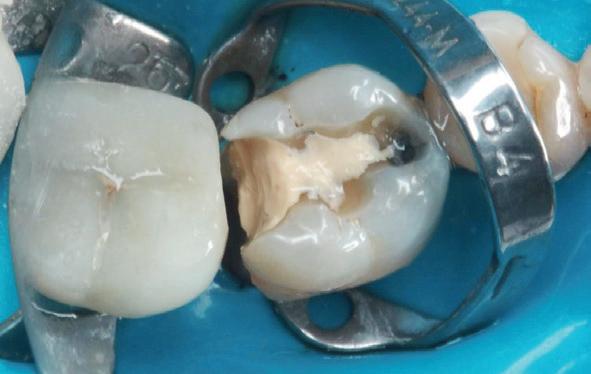

Wees niet spaarzaam met het wegnemen van aanwezig restauratiemateriaal

Misschien wel het belangrijkste onderdeel van de wortelkanaalbehandeling is de opening. Dit is de toegang tot het kanaalstelsel. Voldoende toegang maakt dat de wortelkanalen gevonden - en daarna - goed geprepareerd, gereinigd en gevuld kunnen worden. Anders gezegd, een te kleine of verkeerd geplaatste opening maakt een wortelkanaalbehandeling onnodig moeilijk en verkleint de kansen op een succesvolle behandeling aanzienlijk. Een te kleine opening is een mogelijke oorzaak van instrumentbreuk. Hoe zorg je voor een goede opening? Aan de hand van een casus die naar mij is verwezen, laat ik zien hoe je een goede opening maakt en wat de gevolgen zijn van een te kleine en verkeerd geplaatste opening.

Voordat je aan een wortelkanaalbehandeling begint, zorg je voor (of maak je) een goede beginfoto waar het te behandelen gebitselement volledig op staat afgebeeld. Deze foto geeft essentiële informatie: de grootte van de pulpakamer en de ligging ervan; het aantal en de vorm van de wortels en de breedte van hun wortelkanalen en de lengte van de wortels. Hiermee kan je de DETI-score bepalen en de moeilijkheidsgraad inschatten. De grootte en de ligging van de pulpakamer op de röntgenfoto in combinatie met de ideale anatomische vorm, zoals in foto 1 is aangegeven, bepaalt de uiteindelijke vormgeving van de opening. Bij de molaren liggen de kanaalingangen in de buurt van de knobbeltoppen. Als die niet meer in originele staat

(kroon, restauratie) zijn, kan je ook de wortel gebruiken. Soms moet je net subgingivaal sonderen, maar de kanaalingang ligt in het middel van de wortel. Als je die plek visualiseert en projecteert op je opening, boor je de goede kant op. Nog een tip: wees bij het openen niet spaarzaam met het wegnemen van aanwezig restauratiemateriaal (wees wél spaarzaam met het onnodig wegnemen van tandweefsel).

3. De opening is vrij klein gekozen. In rood is de ideale opening aangegeven, de tandarts had veel meer restauratiemateriaal mogen wegnemen.

7. Hierop is nog eens de correcte opening te zien. Ik heb veel van het aanwezige amalgaam weggenomen om zoveel mogelijk ruimte te krijgen. Ook is te zien hoe ik het mesiobuccale kanaal heb moeten verbreden om bij het instrument te komen. Het palatinale kanaal is niet zichtbaar op deze afbeelding.

Als ik de patiënte zie, valt me op dat de opening die de tandarts gemaakt heeft, nogal klein is (foto 3). Eigenlijk is daar niet zoveel reden toe; als ik een ideale opening inteken (in rood), dan loopt een groot deel door restauratiemateriaal. Overwogen kan worden om de aanwezige mesiale box met restauratiemateriaal weg te halen als dat het zicht op de pulpakamer vergroot – ik verwijs naar de tip hierboven (wees bij het openen niet spaarzaam met het wegnemen van aanwezig restauratiemateriaal).

Onder microscopie en met een LN boortje zoek ik het instrumentje op. Na verificatie verwijder ik het door

met een ultrasone tip (Spartan CPR 8, bruin) rondom het vijltje materiaal weg te nemen, waardoor deze als het ware uitgegraven wordt. WaveOne vijltjes zijn irritant om te verwijderen, het nikkeltitanium materiaal wil naar een oorspronkelijke vorm (een rechte vorm) terugbuigen en daarom drukt het zich steeds vast bij het verwijderen. Staal is vaak makkelijker te verwijderen. Maar het lukt me en de wortelkanaalbehandeling kan worden afgemaakt.

Het verwijderen van een afgebroken instrument kost altijd relatief veel (gezond) tandweefsel en kent veel risico op perforatie of andere schade. Daarom is het altijd belangrijk om goed te overwegen of een vijl verwijderd moet worden.

Maar beter nog is om te voorkomen dat een vijltje afbreekt door bij de opening voldoende te prepareren voor goed zicht en voor wat we noemen een ‘straight line access’. Goede voorbereiding is het halve werk.